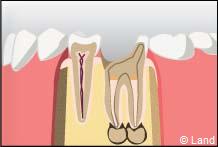

Reconstitution méthode directe avec un matériau composite associé à des tenons radiculaires